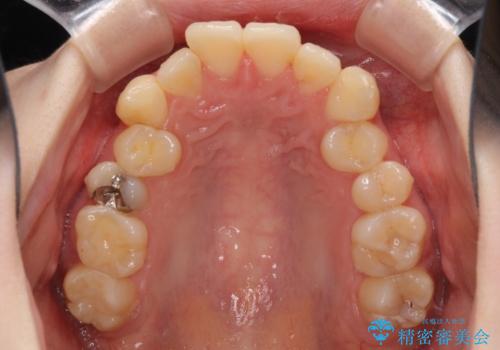

デコボコ歯列をきれいに インビザラインによる矯正治療

- 上下歯列全体のデコボコを気にして来院された患者様です。

主に下顎歯列全体の後方移動とIPR(歯と歯の間を削る)によってデコボコが解消するように設計し、インビザラインにより治療を行うこととしました。

奥歯の知覚過敏が顕著となり、その影響で奥歯の咬み合わせ改善のための顎間ゴムの装着ができず、咬合を仕上げるまでに長い期間を要することとなりました。